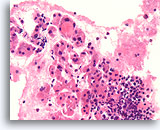

Afbeelding 15

Benigne, hyperplastisch/adenomatoïde nodule, schildklier FNA, celblok.

Dicht fibreus weefsel (niet actief desmoplastisch) met hemosiderine en beduidend atrofische, afgeplatte follikels kunnen worden waargenomen.

40X

Afbeelding 15

Benigne, hyperplastisch/adenomatoïde nodule, schildklier FNA, celblok.

Dicht fibreus weefsel (niet actief desmoplastisch) met hemosiderine en beduidend atrofische, afgeplatte follikels kunnen worden waargenomen.

40X